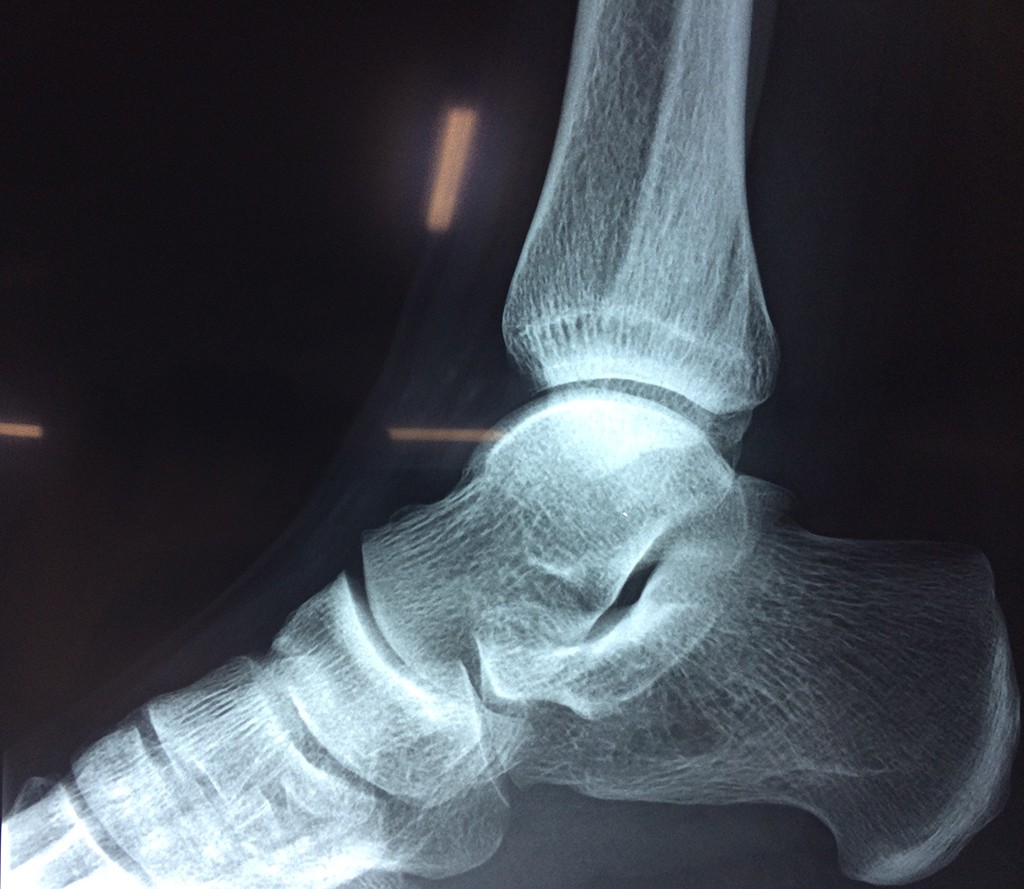

Una fractura de tobillo es la rotura de uno o más de los huesos del tobillo. Estas fracturas pueden ser:

- Parciales (el hueso está sólo parcialmente fisurado, no del todo).

- Completas (el hueso está perforado y está en 2 partes).

- Producirse en uno o ambos lados del tobillo.

Algunas fracturas de tobillo pueden requerir cirugía si:

- Los extremos de los huesos están desalineados entre sí (desplazados).

- La fractura se extiende hasta la articulación del tobillo (fractura intra-articular).